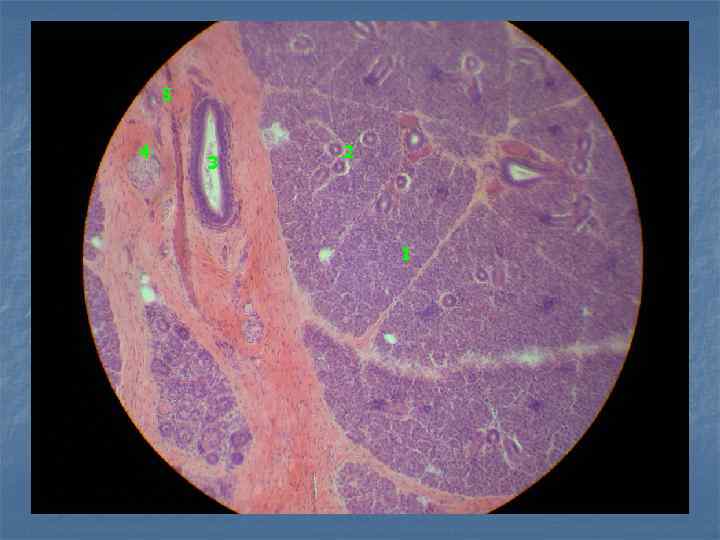

Пр. 8. Поджелудочная железа. Окраска: гематоксилин и эозин. Увеличение: малое. островок Лангерганса ацинус междольковый выводной проток прослойки соединительной ткани междольковые сосуды

Пр. 8. Поджелудочная железа. Окраска: гематоксилин и эозин. Увеличение: малое. ацинус островки Лангерганса

3 1 5 2 4 5 2